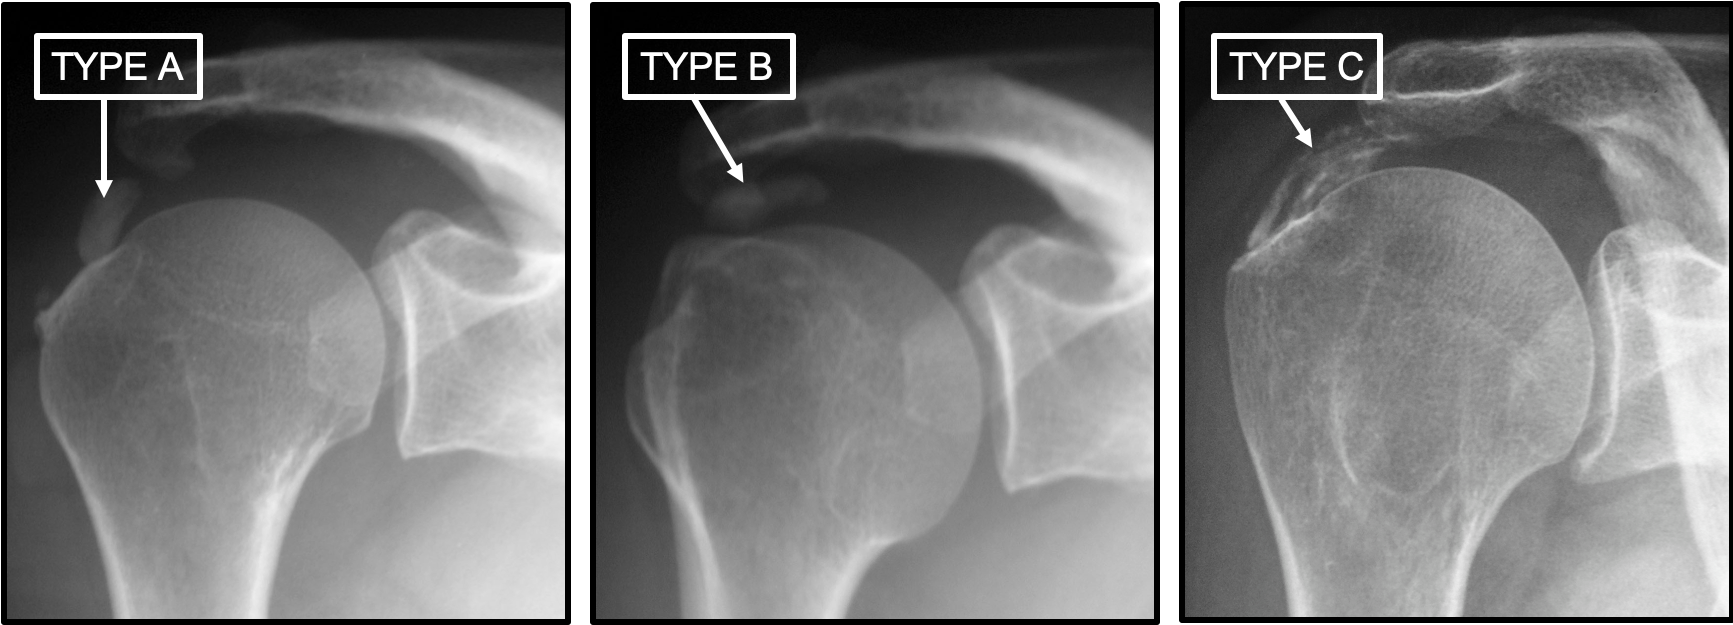

Le couple radiographie/échographie dans les tendinopathies calcifiantes de l’épaule Figure 3

Résumé. La tendinopathie calcifiante de l’épaule est une affection fréquente dont les modalités du traitement restent débattues. Les auteurs de ce symposium ont revu rétrospectivement 450 patients opérés sous arthroscopies pour une tendinopathie calcifiante de l’épaule, avec une imagerie systématique de la coiffe des rotateurs.. Si la calcification a une seule définition, elle a plusieurs étiologies, selon l’endroit où elle se matérialise. De l’épaule aux artères coronaires en passant par les seins et la prostate, tour d’horizon des causes et des traitements de ces dépôts plus ou moins douloureux et graves. Sommaire.